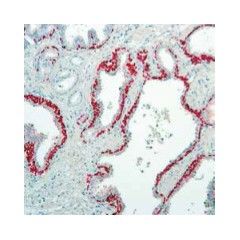

Description: Mouse anti-p40, CE certified (IVD) Isotype: IgG1 Immunogen: Amino acid residues 5 – 17 of human p40 Specificity: This antibody is designed for the specific localization of p40 (or ΔNp63), a truncated p63 protein, in formalin-fixed, paraffin-embedded tissue sections. Anti-p40 receptor antibody is intended for in vitro diagnostic use. Incubation Time: 30-60 min Substrate/Buffer: Mouse monoclonal antibody in TBS with carrier protein and preservative for stabilisation. Technical Specifications: Pre-treatment: Heat Induced Epitope Retrieval (for example in Citrate buffer pH 6.0)Control tissue: Lung squamous cell carcinomaWorking dilution: None Protocol: The recommended positive control tissue for this antibody is lung squamous cell carcinoma. We recommend carrying out a positive and a negative control with every staining run.